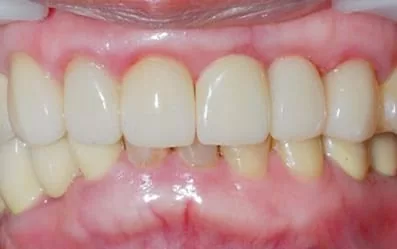

治療前:左上大門牙撞斷

治療後:微創立即植牙恢復美麗外觀

製作全瓷冠,是不是完全看不出來曾經接受2顆植牙呢!